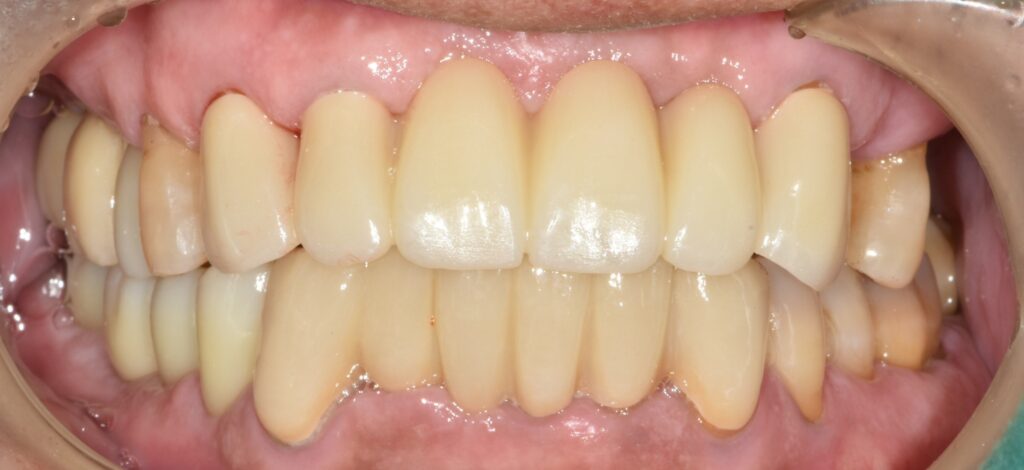

치료가 깔끔하게 잘 된 것 같습니다. 오른쪽 어금니도 얼른 치료해 드리고 싶은데 환자분 개인 사정으로 인해

한쪽만 치료한 것이 못내 마음에 걸렸습니다만 그래도 식사를 편하게 잘하시게 되어 보람찼던 치료 케이스였네요.